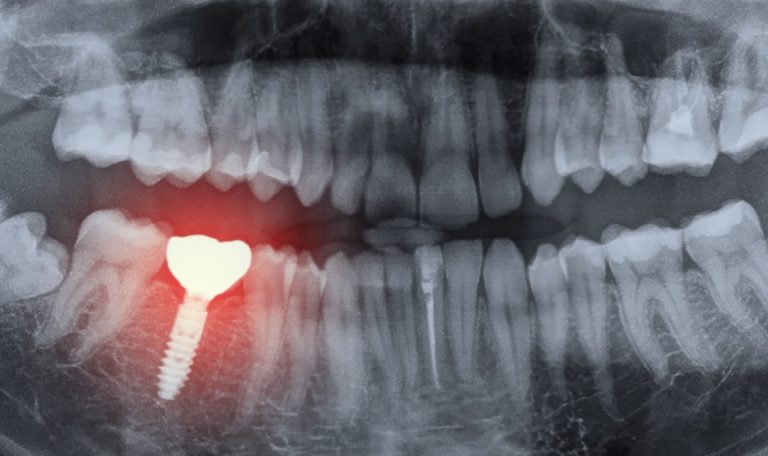

İmplant tedavisi iyileşme süresi ve tedavi aşamaları, diş eksikliği yaşayan birçok kişinin aklındaki en önemli konular arasında yer alır. Modern diş hekimliğinin sunduğu en etkili çözümlerden biri olan implant tedavisi, estetik ve fonksiyonel açıdan uzun vadeli sonuçlar sunar. Ancak..